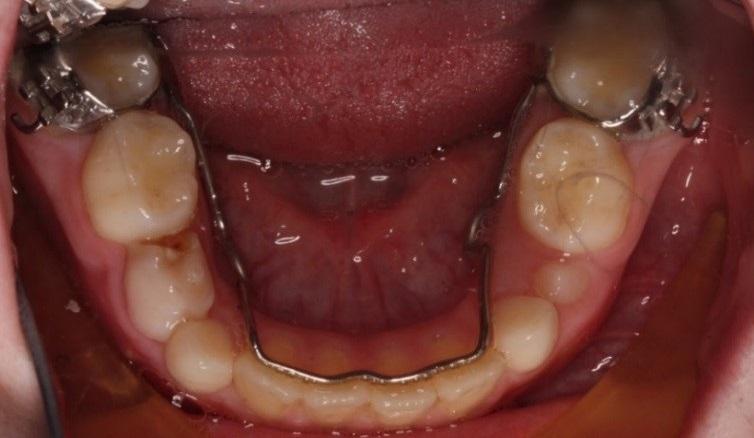

Lingual arch holds the permanent teeth at the back and front of the mouth in place so that the rest of the teeth have room to erupt between them. It is usually left in place until all the permanent teeth have erupted.

Palatal arch holds the main permanent teeth in place so that the rest of the teeth have room to grow. It is usually left in place until all the permanent teeth have erupted.